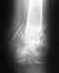

После операции по изменению вальгусной деформации стопы большой палец ноги не поднимается вверх

Чувствительность пальца сохранена, вниз движение сохранено, движение наверх невозможно.После операции прошло 2,5 недели.Как узнать это опухлость может нерва не спала или нерв поврежден был?В первом случае только ждать и спокойствие ноги соблюдать?Во втором случае что нужно делать сейчас? какие меры предпринять чтобы сохранить двигательную способность в будущем?Спасибо!